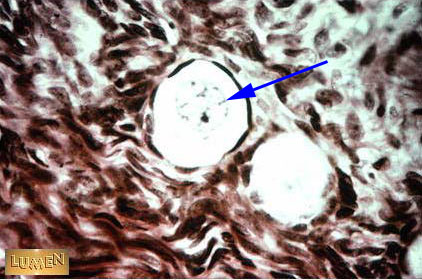

Primary Follicle